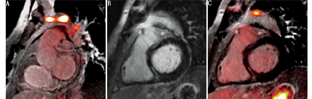

4.CMR/PET联合成像。尽管CMR与PET检测到的CS组织病理学特征不同,这2种技术间的互补作用尚未明确。CMR/PET联合成像的优点是通过CMR识别纤维化和18F-FDG PET评估炎性反应,以对心脏功能进行准确评估。基于联合成像效果有4种模式:第一种是CMR阳性、PET阳性,其中LGE与18F-FDG局灶性摄取增加一致的病灶可能代表活动性CS(图3);第二种是CMR阳性、PET阴性,CMR上可见LGE但无18F-FDG摄取的病灶可能继发于伴心肌瘢痕的非活动性CS(图4);第三种是CMR阴性、PET阴性,LGE和18F-FDG摄取均未见的部位可能代表正常心肌;第四种是CMR阴性、PET阳性,即未见LGE但可见18F-FDG摄取增加(局灶性、弥漫摄取伴局灶性增高、弥漫性),可能是心肌糖代谢抑制失败或心肌正常的生理性摄取造成的假阳性结果,但在某些情况下,LGE阴性的早期CS也可出现这种模式。

Vita等[54]的一项研究对107例疑诊为CS的患者同时使用CMR和PET进行评估,91例(85%)LGE为阳性的患者中,60例(66%)18F-FDG摄取异常,提示存在活动性炎性反应;LGE和18F-FDG摄取均为阳性的患者患CS的概率更高,这些患者行免疫抑制治疗的比例也更高。

Dweck等[55]的一项研究采用CMR/PET联合成像监测了25例患有活动性结节病的患者,该研究的特点是同时采集,采用靶-正常心肌最大比值来定量评估18F-FDG摄取;活动性CS(CMR阳性,PET阳性)的靶-正常心肌最大比值较非活动性CS或假阳性(CMR阴性,PET阳性)的比值高50%[分别为1.6(1.3,1.9)和1.1(1.0,1.1);P<0.001]。这项研究结果还显示,使用联合成像方法检测活动性CS具有较高的灵敏度和特异性,T2 mapping结果与靶-正常心肌比值呈正相关,但并无统计学意义;通过约登指数计算出的最大靶-正常心肌比值的最佳阈值为1.2,诊断灵敏度为100%,特异性为94%。此外,其比需用灌注显像剂来评估心肌瘢痕的18F-FDG PET辐照剂量低(8.2±1.5) mSv。